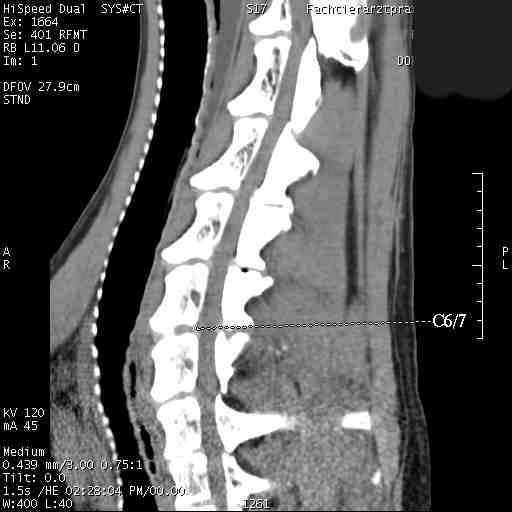

Im folgenden Beispiel sieht man computertomografische Bilder der Halswirbelsäule einer Dogge mit folgender Diagnose: Knöcherne Stensoe C3/4 [= 3./4. Halswirbel], sanduhrförmige Kompression des Myelons auf der Höhe C3/4, Bandscheibenvofall C6/7 [= 6./7. Halswirbel], Myelon mit seitlicher Abweichung nach links : Im Ergebnis eine Halswirbelstenose an den beiden Stellen mit Kompression des Myelons, die zu den Lähmungserscheinungen führt.